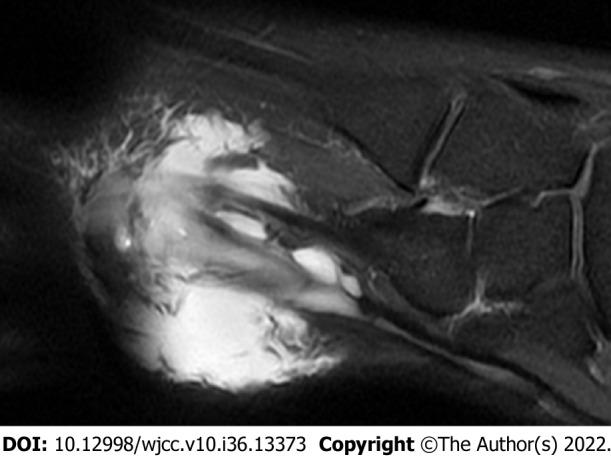

We present the case of a 32-year-old man with an intratendinous ganglion of the second extensor digitorum brevis (EDB) tendon that recurred after ganglion excision. Magnetic resonance imaging (MRI) performed before the first surgery was reviewed to analyze the causes of the recurrence. We confirmed that there was a lack of satellite detection. After recurrence, MRI revealed an extra-tendinous lesion, tenosynovitis, and intratendinous ganglion of the second EDB tendon. Since the second EDB tendon can compensate for the extrinsic muscle, resection was performed alone. In addition, meticulous excision and synovectomy were performed for extra-tendinous lesions and tenosynovitis, respectively. The patient returned to daily life without any functional problems or recurrence.

我们报告一例32岁男性,其第二趾短伸肌腱的腱鞘内腱鞘囊肿在囊肿切除后复发。回顾首次手术前进行的磁共振成像(MRI)以分析复发原因。我们确认存在卫星病灶未被发现的情况。复发后,MRI显示第二趾短伸肌腱有腱外病变、腱鞘炎和腱鞘内腱鞘囊肿。由于第二趾短伸肌腱可代偿外在肌,故单独进行了切除。此外,分别对腱外病变和腱鞘炎进行了细致的切除和滑膜切除术。患者恢复了日常生活,无任何功能问题或复发。